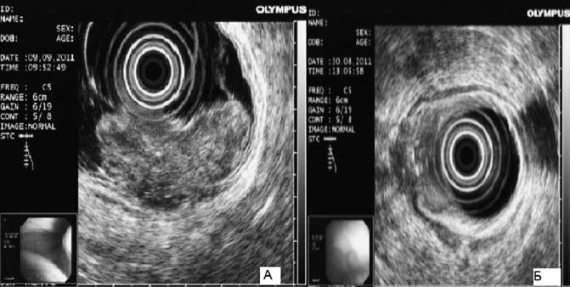

Рис. 63. Эндоскопическая ультрасонография пищевода при раке желудка: А – большая опухоль; В – небольшая опухоль с прорастанием мышечной оболочки

Эндоскопическое ультразвуковое исследование. Эндоскопическая ультрасонография существенно расширяет возможности диагностики рака верхних отделов желудочно‑кишечного тракта. При обследовании больных с опухолями кардиоэзофагеальной зоны эндоскопическое УЗИ позволяет выявить точные границы поражения стенки пищевода и желудка. При этом существенную роль играет решение вопроса о наличии перехода опухоли на пищевод (рис. 63).